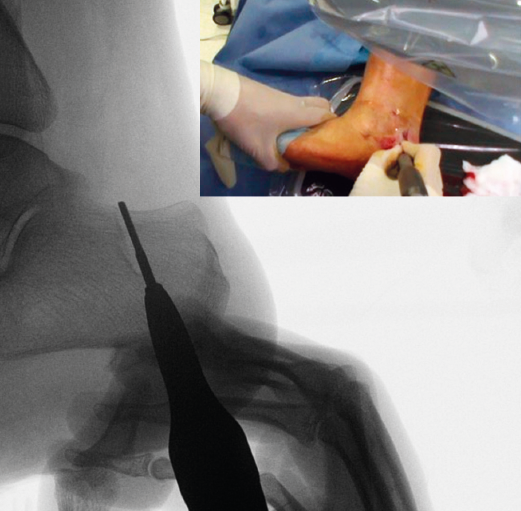

Figura 5. Imagen fluoroscópica del trazo dorsal de la osteotomía y su correspondencia en cirugía.

La fresa se coloca en línea con el trazo de osteotomía dibujado en la piel, primero el dorsal y después el plantar (Figuras 5 y 6), y va cortando la pared lateral y el hueso esponjoso del calcáneo y progresando paulatinamente hasta alcanzar la segunda cortical y cortarla cuidadosamente. Se recomienda no superar en 6.000 rpm la velocidad de la fresa para evitar la osteonecrosis térmica. A pesar de que el procedimiento se realiza sin isquemia para que la sangre refrigere el calor de la fresa, se recomienda que el ayudante aporte suero salino para contribuir a tal efecto.